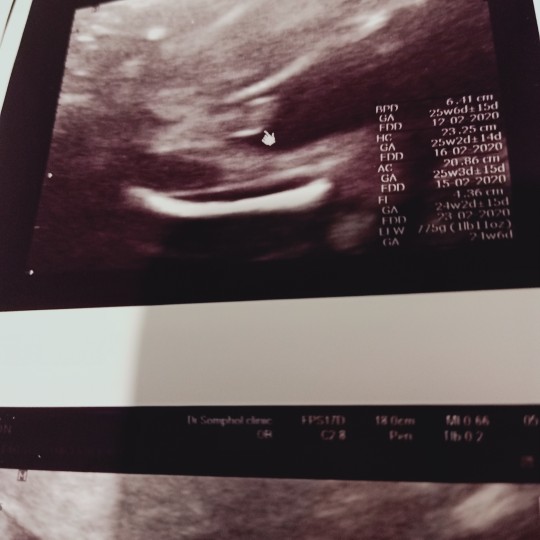

18w จู๋โผล่แล้วจ้า?

แม่ๆบ้านไหน ซาวด์แล้วได้เพศไหนกันบ้างคะ บ้านนี้อยากได้ลูกชายอยู่แล้ว ได้ลูกชายสมใจเลยคะ?

บ้านนี้เห็นชัดเจนมากค่ะตอนหมอให้ดูในใจลุ้นมากอยากได้ ผญ น้องอ้าขากว้างมากแอบเสียใจนิดๆแต่ก้อดีใจค่ะ เพราะยังใงก้อลูก

เห็นคุณหมอเริ่มซาวด์ 4 มิติตอน 15 สัปดาห์นะคะ และก็ซาวด์ 4 มิติ + กับธรรมดาตลอด แต่บางโรงพยาบาลหรือบางคลีนิคอาจซาวด์แค่ครั้ง 2 ครั้งหรืออาจจะเสียค่าใช้จ่ายเพิ่มเติม คุณแม่ก็ซาวด์ตอน 24- 28 สัปดาห์น่าจะชัดสุดละค่ะ ถ้าอายุครรภ์มากกว่านั้น น้องจะตัวใหญ่ขึ้น อาจทำให้เห็นไม่ชัดเจน ลองปรึกษาคุณหมอที่ฝากครรภ์ดูนะคะ